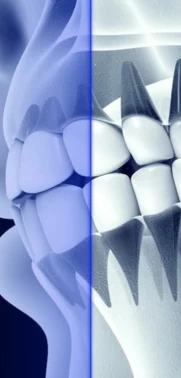

Мостовидные протезы — эффективный способ восстановить зубной ряд при отсутствии одной или нескольких единиц подряд. Для этого мы сделаем конструкцию из искусственных зубов. Потом закрепим их на опорных единицах или имплантах.

Мостовидный протез — это несъемная ортопедическая конструкция. Для ее установки обязательно нужны целые единицы рядом или установка имплантов. Именно на них придется нагрузка от протеза.

Такой подход ограничивает число зубов, которые можно восстановить. В большинстве случаев мост ограничен 4 единицами. И даже так может потребоваться использовать несколько опорных зубов с каждой стороны, чтобы уменьшить нагрузку на них.

Мост обязательно требует обточки зубов. Нам придется снять немного здоровых тканей, чтобы коронка плотно прилегала и не мешала жеванию, смыканию челюсти. Обойти это можно только, если зуб сильно поврежден и вместо него будем ставить имплант.